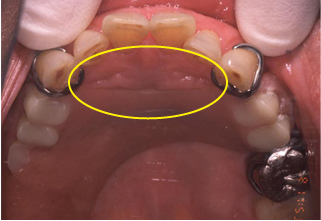

発音において問題のある義歯

図4

図4は別の症例であるがやはり発音と装着時の違和感を訴えている。

この症例では口蓋の後方の床の厚みに問題がある。まず、口蓋の後方は“カ”行、“ガ”行が関係がある(図中、青マル部)。この部分の床が厚かったり、長かったりすると患者は発音がしづらくなる。特に“ガ”行は鼻濁音になるので歯科医師にもわかりやすい。

その際には義歯床を薄くまた短くすることが重要である。また口蓋の後方は特に上顎結節の付近は基本的に顎堤の吸収は起きにくい部位である。そのため義歯床の研磨面形態が最後方人工歯からハミュラーノッチにかけて図(黄色線)にあるように内側に走行することが多く見られる。発音を含め口腔内が狭く感じると患者が訴えた場合、上顎結節付近の口蓋側の研磨面形態を薄くして対応すると快適な義歯となる。